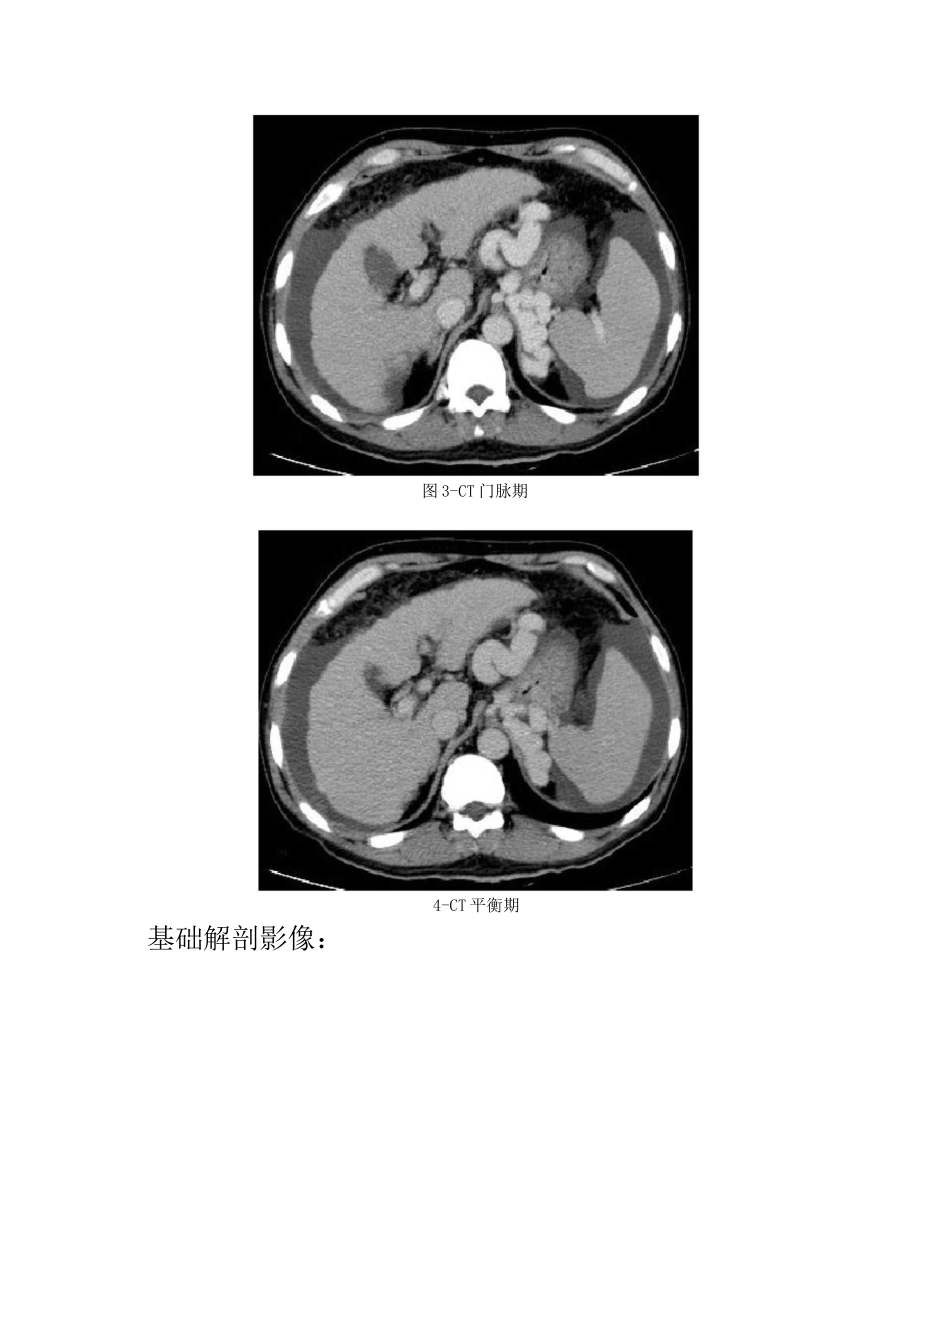

肝硬化 CT 诊断要点及鉴别诊断病史:患者,男,52 岁,因乙肝病史 8 年,腹胀、黑便、血便 5 天。图 1-CT 平扫图 2-CT 动脉期图 3-CT 门脉期4-CT 平衡期基础解剖影像:图 5图 5 为所示病例同层面正常腹部 CT 增强门脉期图片,蓝色箭头所示为正常肝脏右叶,其内见强化血管影,黄色箭头所示为正常胃,其内可见高密度对比剂影像,棕色箭头为下腔静脉,白色箭头所示为脾脏,绿色箭头所示为胰腺体尾部,其背侧贴边见强化脾静脉。本图节选自《CT 与MRI 断层解剖学袖珍图谱》。图 1图 2图 3图 4CT 平扫(图 1):蓝色箭头所示为肝脏体积缩小,边缘呈波浪样凹凸不平,白色箭头所示为脾脏体积增大,超过 5 个肋单元,肝脾周围见弧形水样密度影。CT 增强动脉期(图 2)肝脾周围积液对比明显,注意脾脏呈花斑样强化。CT 增强门脉期(图 3)黄色箭头所示为胃底静脉及食管下段静脉、腹主动脉左旁静脉明显扩张走行迂曲 oCT 增强延迟期(图 4)所示见肝脏比例欠协调,可见弥漫大小不等结节影,与肝组织强化程度相同。影像描述:肝脏体积缩小,形态不规整,边缘凹凸不平,各叶比例不协调,肝实质见弥漫结节样等密度影,大小约 0.3-1.3cm,界清,未见强化。脾脏体积增大,密度未见异常。食道下段、胃底区域及腹主动脉左旁见多发迂曲增粗静脉血管影,部分血管汇入左肾静脉。腹腔内可见游离液体影。影像诊断:肝硬化、脾大、腹水、侧支循环开放并胃肾分流分析思路:1. 临床病史:老年男性,乙肝病史 8 年,腹胀、黑便、血便 5 天,均提示肝脏病变致消化道出血可能。2. 部位及形态:肝脏体积缩小,边缘凹凸不平,肝门、肝裂增宽,提示肝硬化可能;其内见多发等密度结节,考虑为再生结节,不除外癌变可能;肝脾周围见水样密度影,提示腹腔积液;胃底区域、食管下段、腹主动脉左旁见迂曲强化血管影,提示侧枝循环开放及左肾静脉、胃底静脉分流。以上均为典型肝硬化表现。最后诊断:肝硬化。知识巩固:肝硬化1.临床表现:常见病因为病毒性肝炎、自身免疫性肝炎及酗酒。早期,肝细胞弥漫性变形、坏死;中晚期大量纤维组织增生,形成再生结节,肝脏变形、变硬,继发门静脉高压,最后可变成不典型增生结节,导致肝细胞癌。常见临床表现为食欲缺乏、腹胀、黄疸、腹水、呕血和肝性脑病。2.影像特点:早期肝脏体积增大,无特征性性。中晚期典型肝硬化 CT示体积缩小,各叶比例失调,边缘凹凸不平,肝门、肝裂增宽,内部密度不均,可见...